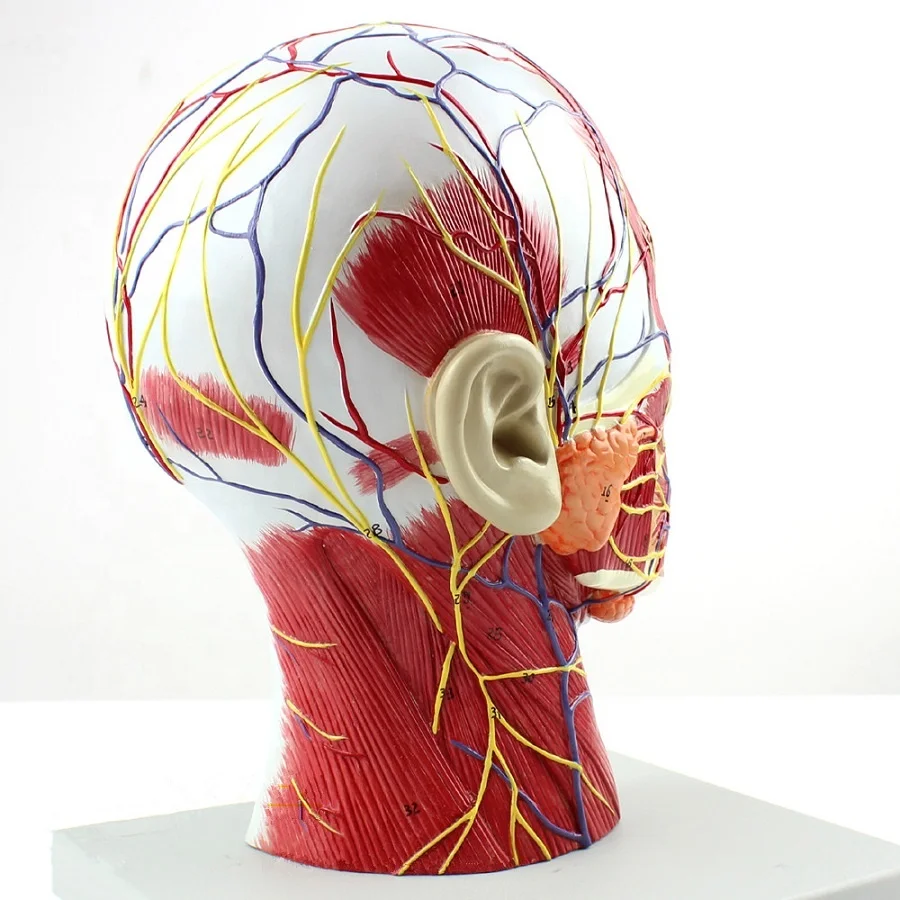

2. Anatomically mimic muscular system with the main superficial arteries, veins and nerves and the area of the neck are demonstrated.

3. 100 positions are displayed.

Size:life size 27*10*20cm